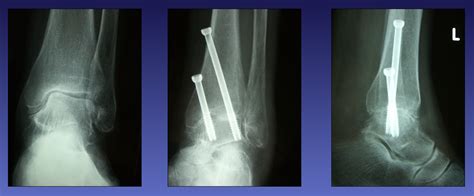

Explore advanced ankle fusion procedures designed to alleviate chronic pain and restore mobility. Learn about the surgical process, recovery timelines, and orthopaedic benefits for patients suffering from severe ankle arthritis. Discover how these effective joint stabilization techniques can improve your quality of life and long-term functional outcomes. Consult a specialist to determine if this surgery is right for you.